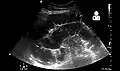

Radiological signs of bowel obstruction include bowel distension and the presence of multiple (more than six) gas-fluid levels on supine and erect abdominal radiographs. Ultrasounds may be as useful as CT scanning to make the diagnosis.[13]